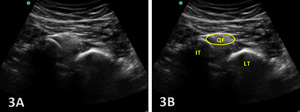

The ischiofemoral space (IFS) is the anatomical interval between the lateral cortex of the ischial tuberosity and the medial cortex of the lesser trochanter of the femur. Within this space lies the quadratus femoris muscle, along with the sciatic nerve and associated vascular structures, all of which are crucial to hip function. Narrowing of the IFS, typically defined as a distance below 1.5 cm, can lead to IFI, a condition characterized by pain and restricted motion in the posterior hip. In addition to the IFS, the quadratus femoris space (QFS)the distance between the hamstring origin on the ischial tuberosity and the insertion of the quadratus femoris muscle—is another critical measurement in assessing IFI.

When the IFS becomes narrowed, compression of the quadratus femoris muscle and the sciatic nerve can occur, leading to the hallmark symptoms of IFI, including deep posterior hip pain and potential nerve-related symptoms. Normal IFS values range from 2 to 2.5 cm, and accurate measurement of this space is crucial for diagnosis. Given that the actual space is highly variable based on the gait cycle or what position the hip is in during testing, and MRI tends to overestimate the measurement,6 MSKUS is the perfect tool for assessing this space either statically or dynamically. Dynamic hip MSKUS can corroborate IFI and space with the change in position of the lower extremity, as well as to assess whether the symptoms are due to other potential causes.7 MSKUS is an invaluable tool for visualizing these structures, offering dynamic, real-time imaging that enhances diagnostic accuracy in cases of suspected IFI .

Narrowing of the IFS: A key indicator of IFI is the decreased distance between the ischial tuberosity and the lesser trochanter. Ultrasound allows for precise measurement of the IFS, particularly at the point of greatest narrowing, which is critical for diagnosing impingement. IFS measurements by MSKUS have been shown to be very similar to those obtained with MRI.15